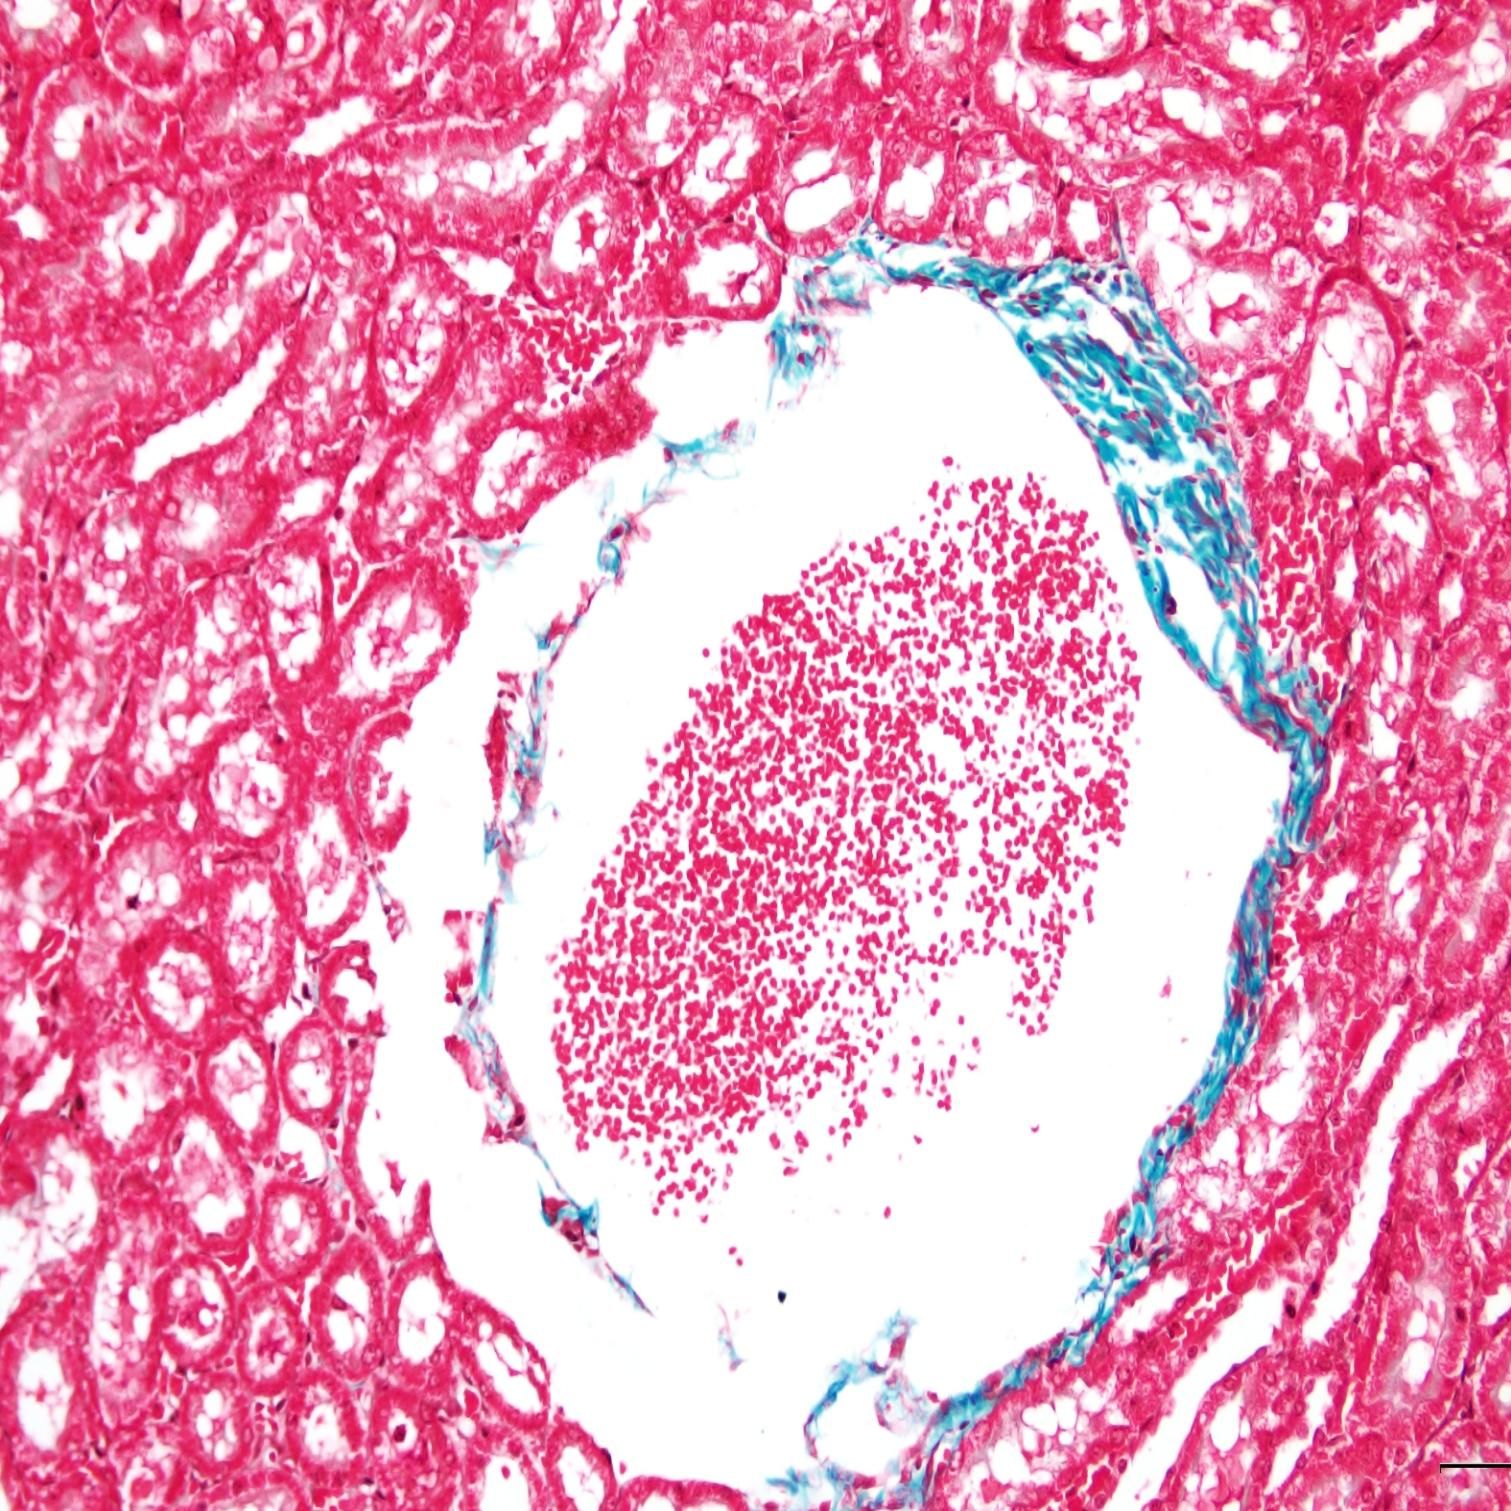

完成以上步驟后,切片中的膠原纖維、黏液和軟骨將呈現藍色(如果使用淺綠色液體,則呈現綠色),細胞質、肌肉、纖維素和神經膠質將呈現紅色,而細胞核將呈現黑色藍色。